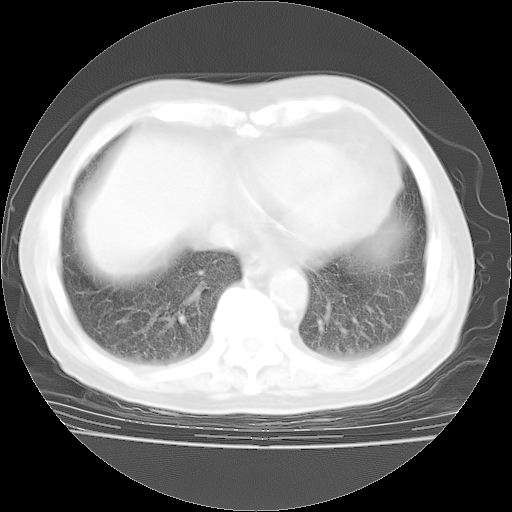

4月28日肺部CT——再次出现类似去年5月9日——透光度降低,“间质性”改变。

4月28日肺部CT——再次出现类似去年5月9日——磨玻璃样、间有“粟粒样”改变。